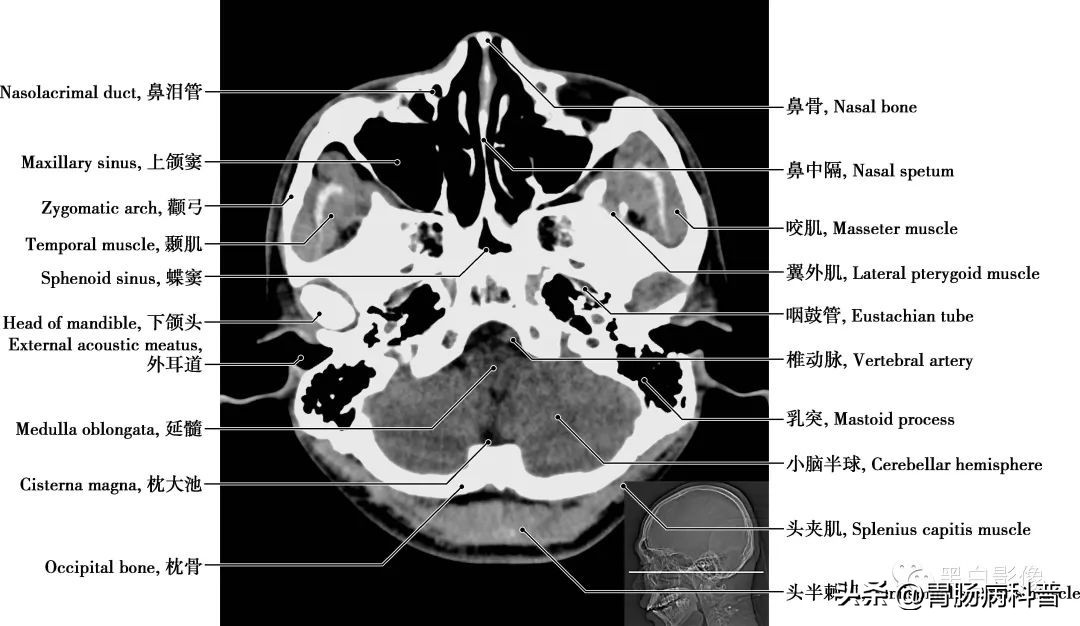

图1-1-18 经下颌头轴位切面

枕大池 又称小脑延髓池,位于颅后窝的后下部,小脑下面、延髓背侧面与枕鳞下部三者之间。向前经小脑溪通第四脑室;向前外经延髓侧面通延髓池。咽鼓管 咽鼓管从鼓室口向内、向前、向下直到咽口,是沟通鼓室与鼻咽部的通道,软骨部平时闭合,仅在吞咽或呵欠时开放,以平衡中耳和外耳的气压,有利于鼓膜的正常振动

图1-1-19 经小脑扁桃体轴位切面

上颌窦 为上颌骨体内的锥形空腔,位于上颌骨体内,窦壁为骨质,覆黏膜,向内侧开口于中鼻道,分为一底、一尖及前、后、上、下四个壁。由于窦口高于窦底部,故在直立位时若有炎性物不易自然流出。外耳道 为外耳门至鼓膜的管道,呈弯曲状,由外向内,先向前上,继而稍向后,弯向前下